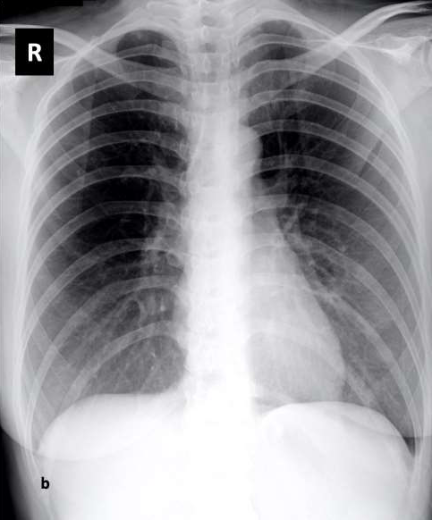

In this sub-section, we concisely inaugurate the benchmark data set, named COVIDx[22], that used in our experiment. To the best of our knowledge, this data set is one of the largest open-access benchmark data set for the number of COVID-19 infection cases, and the total number of 14,914 images for training and 1,579 images for testing, comprising three categories of COVID-19, normal and pneumonia333Access on July 17, 2020. Figure 1 shows sample images from the benchmark dataset, including COVID-19, normal and pneumonia. Table 2 depicts the distribution of images in training and testing sets. To generate the COVIDx, the authors[22] used five different publicly accessible data repositories:

Refer to caption

(a) COVID-19

(b) Normal

(c) Pneumonia

Figure 1: Some image labels available in the benchmark dataset [22]